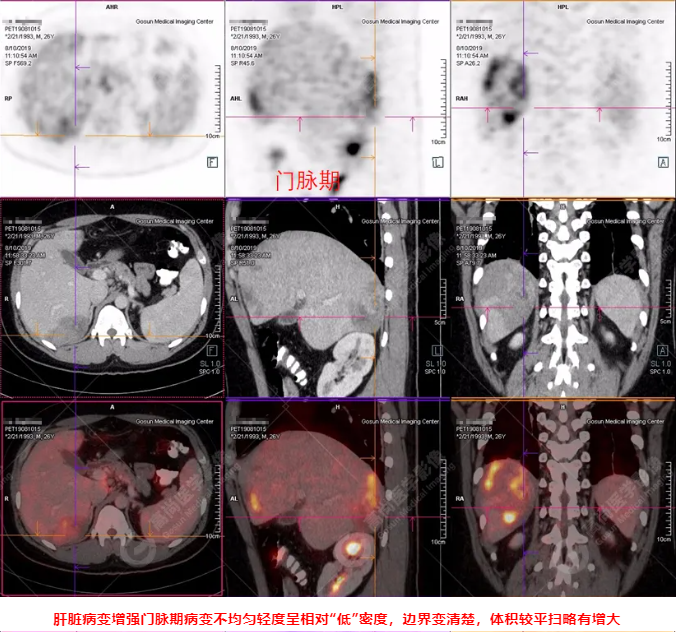

B超及CT檢查發(fā)現(xiàn):肝臟多發(fā)低密度占位。

PET/CT全身圖

PET/CT診斷

嗜酸性粒細(xì)胞增多癥肝浸潤

吡喹酮治療前兩天體溫驟然升高,之后體溫恢復(fù)正常,半個月后CT復(fù)查肝臟病變體積較前明顯縮小、吸收。